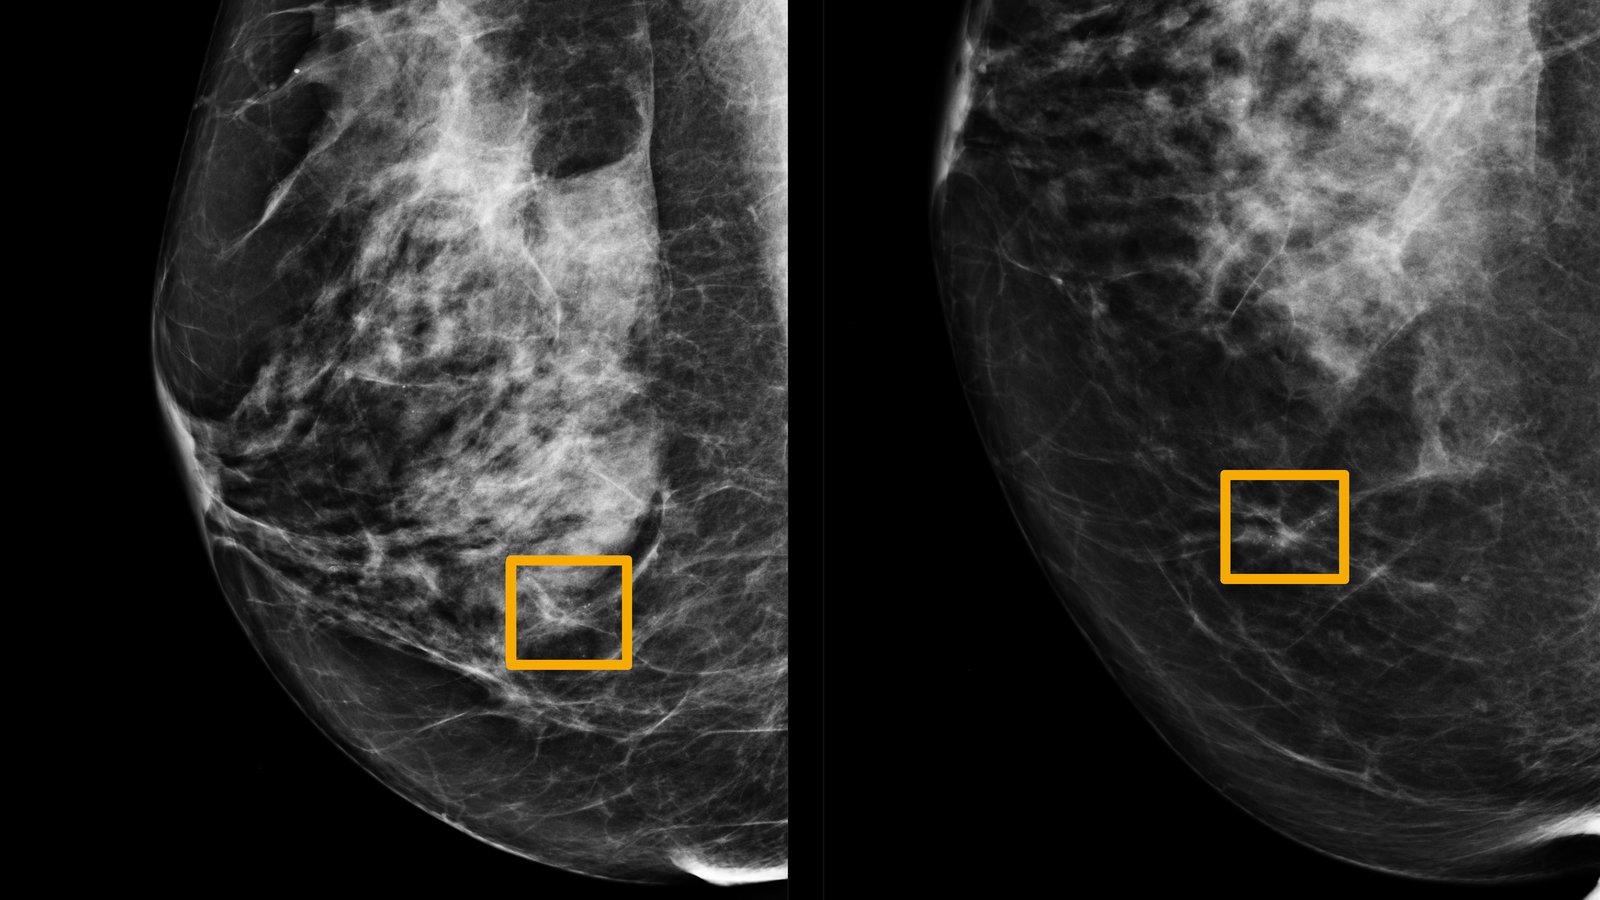

進行乳房造影時,AI能夠分析患者的檢查影像,自動按影像進行乳癌風險評估,方便醫生跟進診斷和治療。

AI可用於輔助醫學影像分析,例如病人進行乳房造影時,AI能夠分析患者的檢查影像,自動按影像進行乳癌風險評估,方便醫生跟進診斷和治療;又如診斷皮膚癌中,AI可用於分析皮膚鏡影像,協助醫生找出影像中的潰瘍;AI也可用於協助分析電腦掃描及磁力共振掃描影像。它懂得從工作中「汲取經驗」,當它分析得愈多,其深度學習演算法會不斷提高影像分析的精準度,分析得愈好。目前已有不少研究顯示,由AI輔助能夠大大減省醫生分析影像的時間,令癌症診斷更有效率,是優秀的影像分析輔助工具。